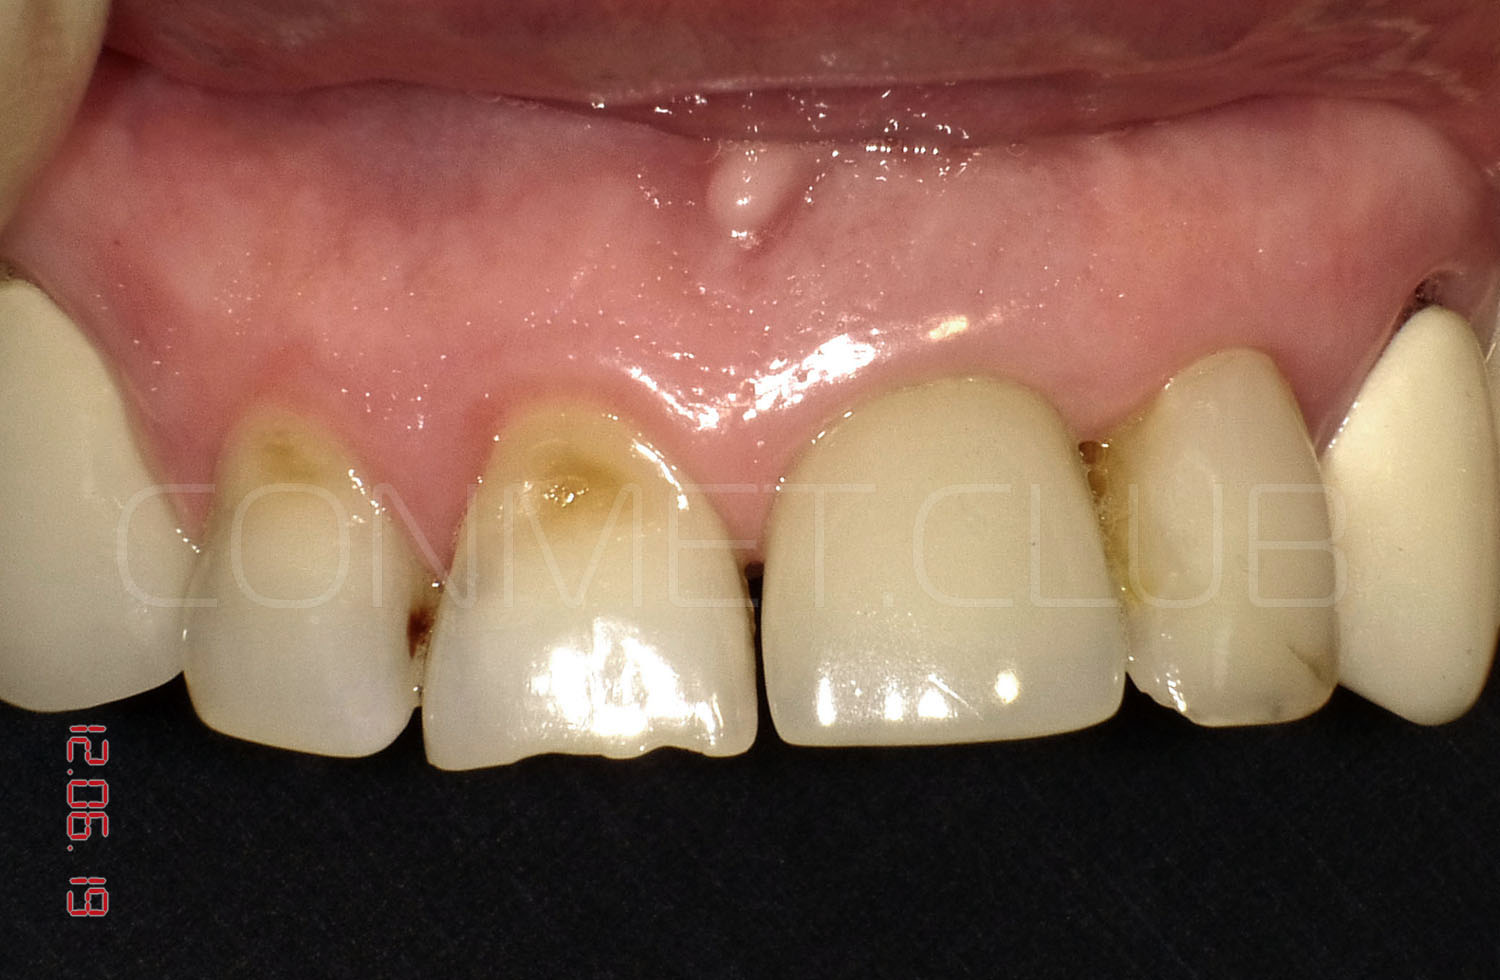

Состояние через 10-15 лет

Фото этой же коронки через 15 лет после операции.

15 лет полноценной функциональной нагрузки.

Контрольная рентгенограмм через 15 лет после операции. Если на рентгенограмме и можно различить небольшую щель между имплантатом и костью на уровне полированной части имплантата, то клинически она полностью отсутствует и не диагносцируется парадонтологическим зондом.